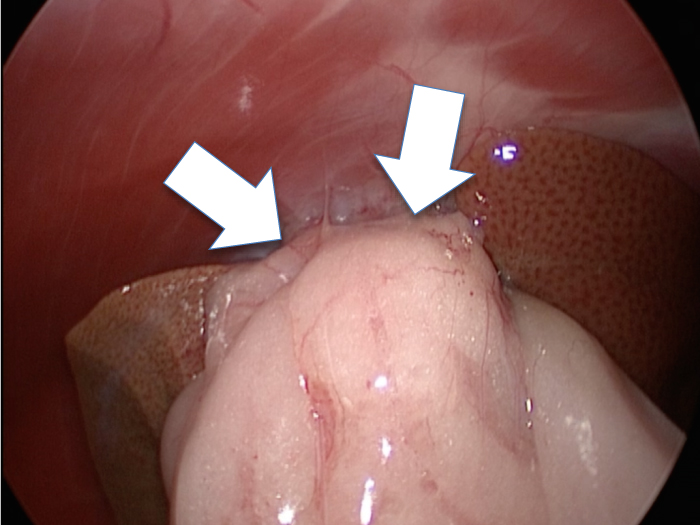

癒着(矢印)がひどく胆嚢を確認することができませんでした。

このように癒着しているときはギリギリで剥がすとひどく出血をおこすことがあるので無理にはがそうとしないで、脂肪の血管に注意しながら脂肪ごと剥がしていきます。